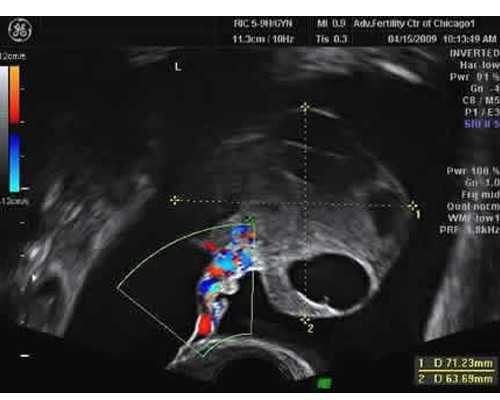

在试管婴儿治疗之前,夫妻双方需要做好身体的全数的检查,其次,女方还需要进行一个检查,以此来了解排卵到底是不是正常的,以及女性的子宫内膜还有一些常规的妇科方面的检查。而男方则需要进行的是精液方面的的检查,另外,在手术开始前,夫妻双方务必要遵医嘱,一定不能胡乱饮食更不能私自服用任何药物,适当应进行一些体育运动。夫妻二人都应该尽量去远离烟酒,避免因此而影响手术的治疗。